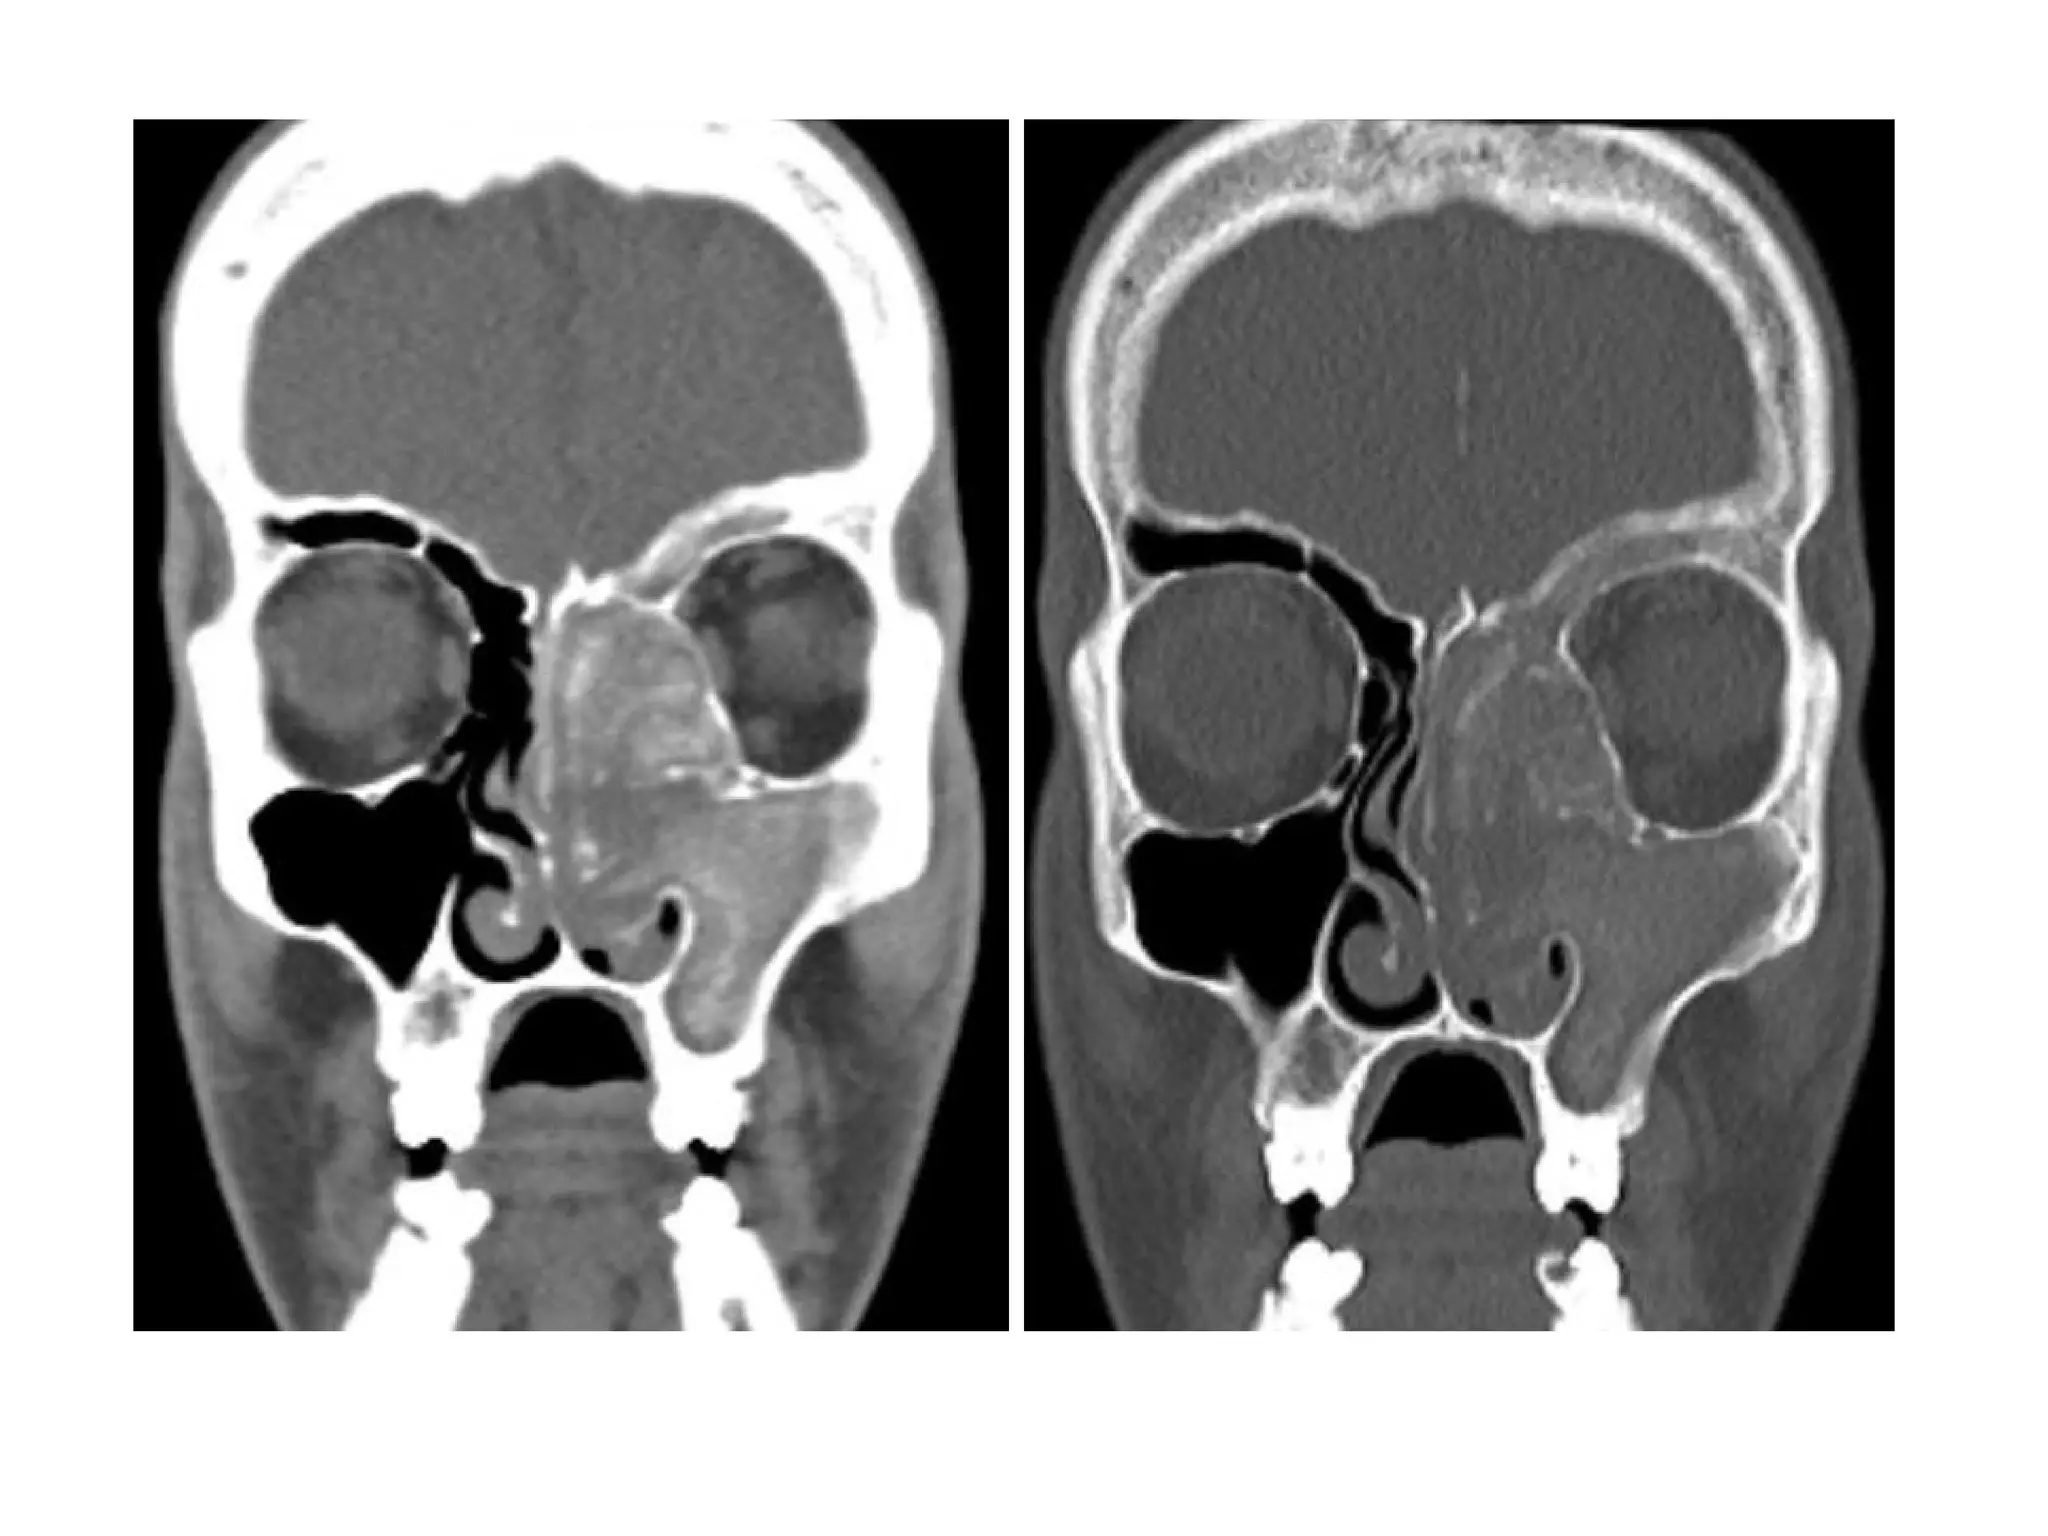

Mucocele of the frontal sinus

Ethmoid mucocele

Right ethmoid mucocele, coronal soft tissue (A) and axial bone

algorithm (B) CT images show a completely opacified, mucus-filled

and expanded right ethmoid sinus, focal dehiscence or erosion of

the right lamina papyracea (arrow, B) is seen

Mucocele of the sphenoid and ethmoid sinuses